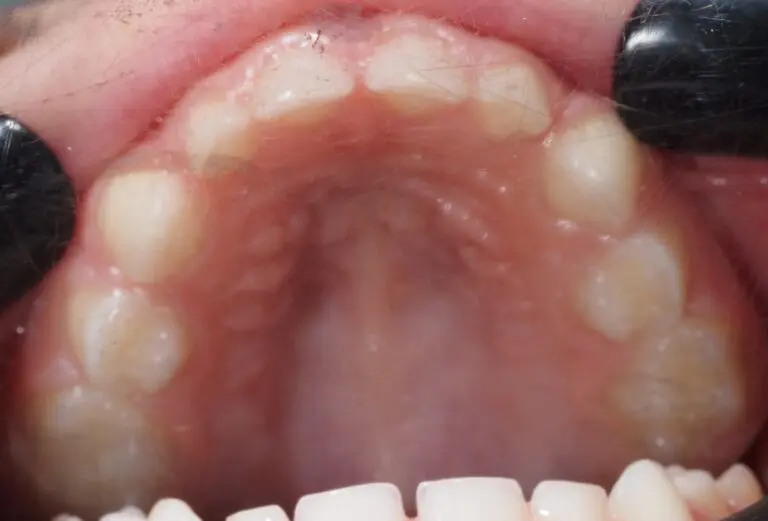

Wpływ wąskiego podniebienia na zdrowie dziecka Jeśli jesteś rodzicem kilkulatka, który jakoś tak szybko się męczy, w…